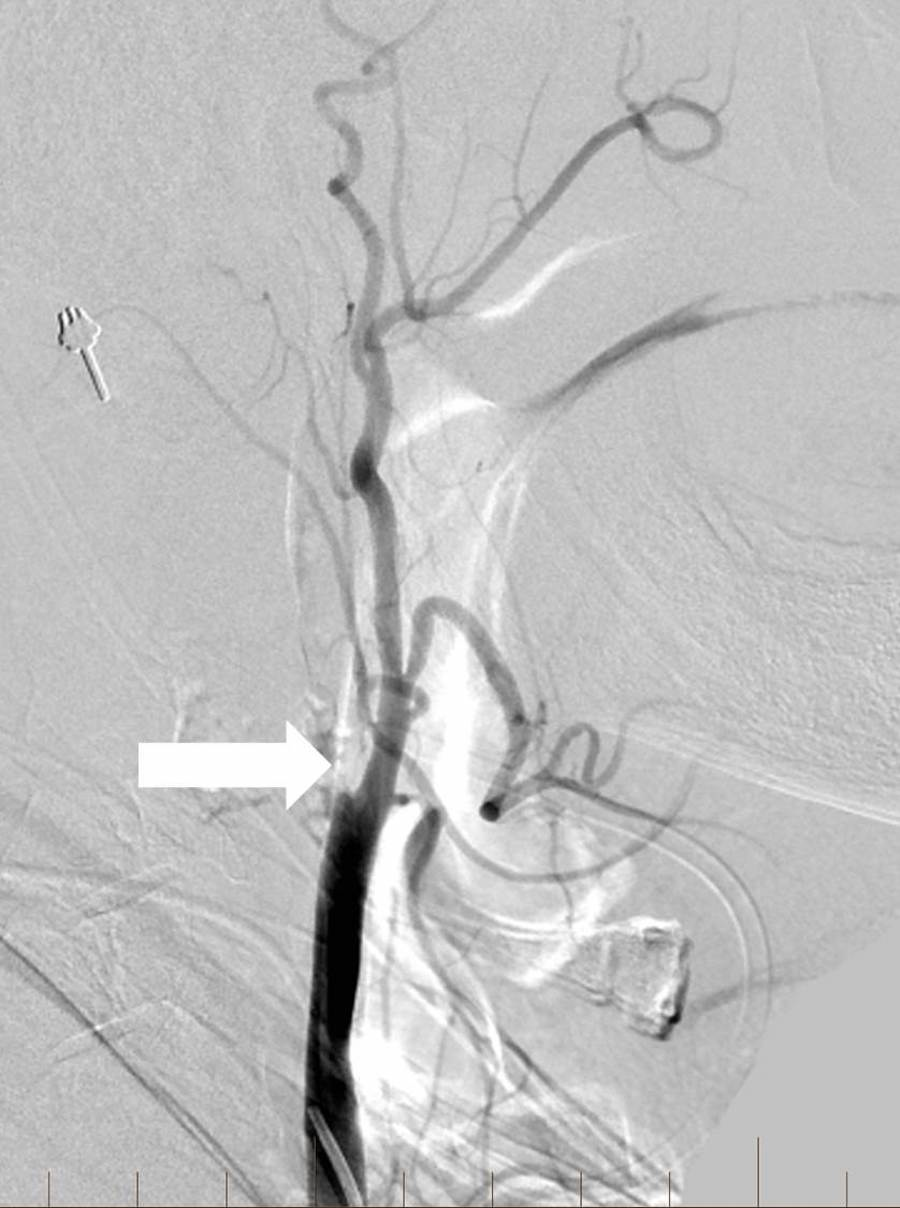

Angioplasty was performed at the level of the severe proximal ICA occlusion using a 4 mm x 20 mm noncompliant balloon. Subsequent angiography demonstrated the progression of contrast into the distal cervical and intracranial segments of the ICA with a persistent severe and irregular stenosis. A decision was then made to stent using distal embolic protection. A 4-mm diameter distal protection device was advanced and deployed in standard fashion within the distal cervical ICA at the level of C1-C2. An eptifibatide infusion was started, and an 8 mm to 6 mm tapered self-expanding carotid stent measuring 40 mm in length was positioned across the lesion and deployed in the standard fashion without angiographic complications. Post-stenting angiography revealed a 90% improvement in the caliber of the occluded vessel without delay in transit time throughout all cervical and intracranial right ICA segments (Figure 2).